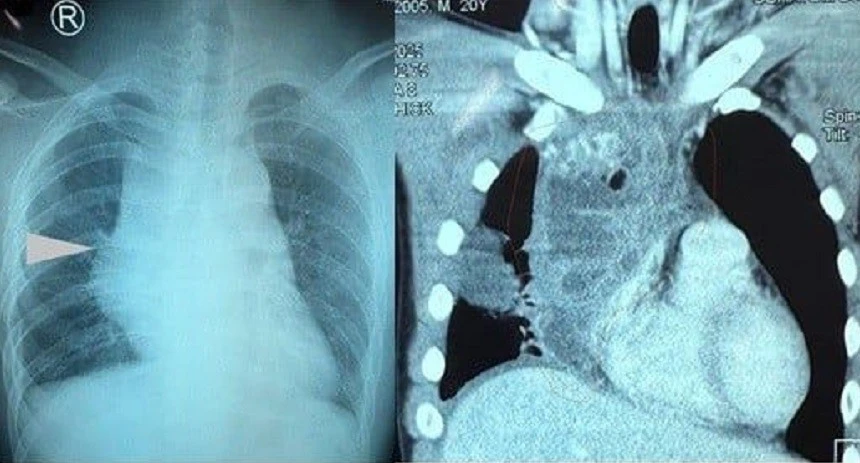

TPO - Các bác sĩ khoa Phẫu thuật Tim – Lồng ngực Mạch máu, Bệnh viện Nhân dân 115 vừa phẫu thuật thành công một trường hợp u quái trung thất hiếm gặp ở người bệnh mới 20 tuổi, khối u lớn chiếm gần trọn lồng ngực phải, chèn ép tim, phổi và tĩnh mạch chủ.